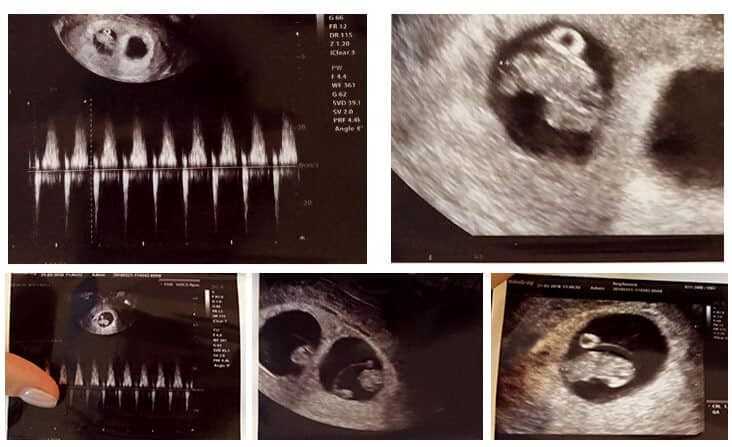

Twins boys, successful from ICSI-NGS

Russian patients trying IVF and fresh embryo transfer 8 times in other countries came to our clinic IVF Phuket.

Successful with twins boys from frozen embryo transfer after ICSI and Illumina-NGS (Feb 2018) at SAFE Fertility Center, Phuket Branch (IVF Phuket) by Dr. Manop Janthanaphan and K. Marina (Russian Personal Assistant). Wait sweet baby-boys in October 2018!